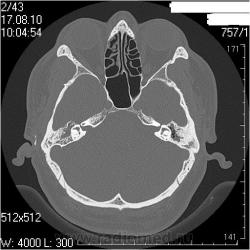

Правая височная кость

Наружный слуховой проход: конфигурация обычная, просвет не сужен, костные стенки ― ровные, четкие.

Сосцевидный отросток: тип строения склеротический, в сохранившихся ячейках отмечаются снижение прозрачности за счет патологических структур.

Воздушные полости среднего уха: пневматизация нарушена полностью за счет мягкотканных (41едН) патологических структур; размеры аттика, адитуса и антрума в пределах нормы. Ширина аттика ― 5,6мм (N=6.4-7мм), адитуса ― 2,1мм (N=3,1-3,3мм), антрума ― 4,6 мм.

Костное устье слуховой трубы: заполнено мягкотканными патологическими структурами.

Слуховые косточки прослеживаются

Внутреннее ухо: размер, форма, положение, плотность и контуры элементов структур внутреннего уха не изменены.

Внутренний слуховой проход: конфигурация не изменена, контуры ровные, четкие, ширина ― 3,2мм (N=4-6мм)

Заключение: КТ- признаки двустороннего хронического среднего отита: склеротические изменения больше выражены в левом сосцевидном отростке; мягкотканные патологические структуры в воздушных полостях среднего уха больше выражены справа; блок костного устья правой слуховой трубы; неполный блок костного устья левой слуховой трубы

Соглашусь с Виталием. Мы делаем височные кости отдельными реконструкциями на правую и левую кость еще по 0,6мм. Здесь не знаю как, но вот по 0,6мм (кстати, так делают в Европе, насколько мне известно) плотность померить - результаты будут от фонаря. И еще мне режет уши - заполнено патологическими структурами. Что за структуры? Андрей Юрьевич, это Ваше описание? Я видел подобные в ММА Сеченова. вообще, мне нравится такой тип описания, когда все четко по полочкам разложено, не надо заниматься, порою, долгим поиском интересующей области в тексте описания. Кстати, достоверного блока устья левой трубы не вижу на представленных томограммах. Похоже, просто не те срезы выбраны. (сразу скажу, я не спец по ушам , хочется разобраться) Вернее сказать, вообще не вижу блоков. Покажите, если не трудно

А засада (что НЕ ТАК), для меня здесь вот в чем. У пациента клиника левостороннего отита (многолетний анамнез, отделяемое из уха, перфорация перепонной барабанки при отоскопии), а справа клиники нет совсем. После КТ ЛОРы дописали рубец на правой перепонке, и выписали + с адгезивныи отитом справа (хотя при адгезивном отите КТ-картина должна быть несколько иная).